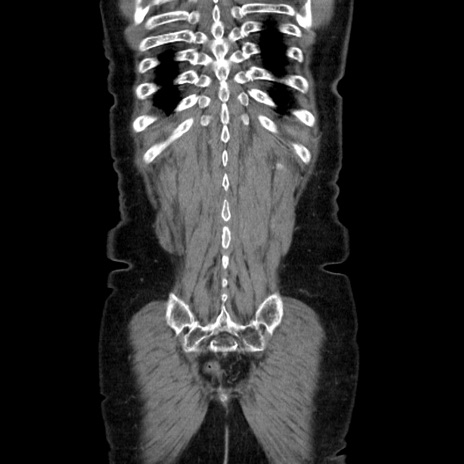

症例5(冠状断像)

【症例】70歳代女性

【身体所見】意識清明、BT 36.5℃、BP 165/106mmHg、HR 80bpm、SpO2 98%、腹部:膨満、軟、自発痛・圧痛なし、触診にて不快感あり、腸蠕動音:減弱